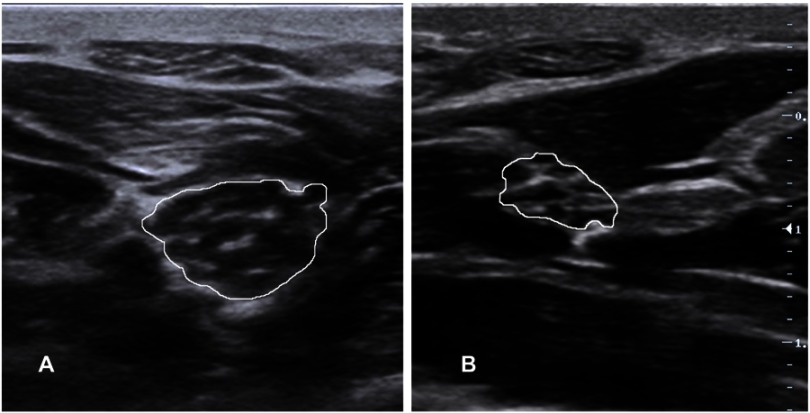

Amyotrophic lateral sclerosis (ALS) is a devastating neurodegenerative disorder characterized by dysfunction at multiple levels of the neuraxis. It remains a clinical diagnosis without a definitive diagnostic investigation. Electrodiagnostic testing provides supportive information and, along with imaging and biochemical markers, can help exclude mimicking conditions. Neuromuscular ultrasound has a valuable role in the diagnosis and monitoring of ALS and provides complementary information to clinical assessment and electrodiagnostic testing as well as insights into the underlying pathophysiology of this disease. This review highlights the evidence for ultrasound in the evaluation of bulbar, limb and respiratory musculature and peripheral nerves in ALS. Further research in this evolving area is required.